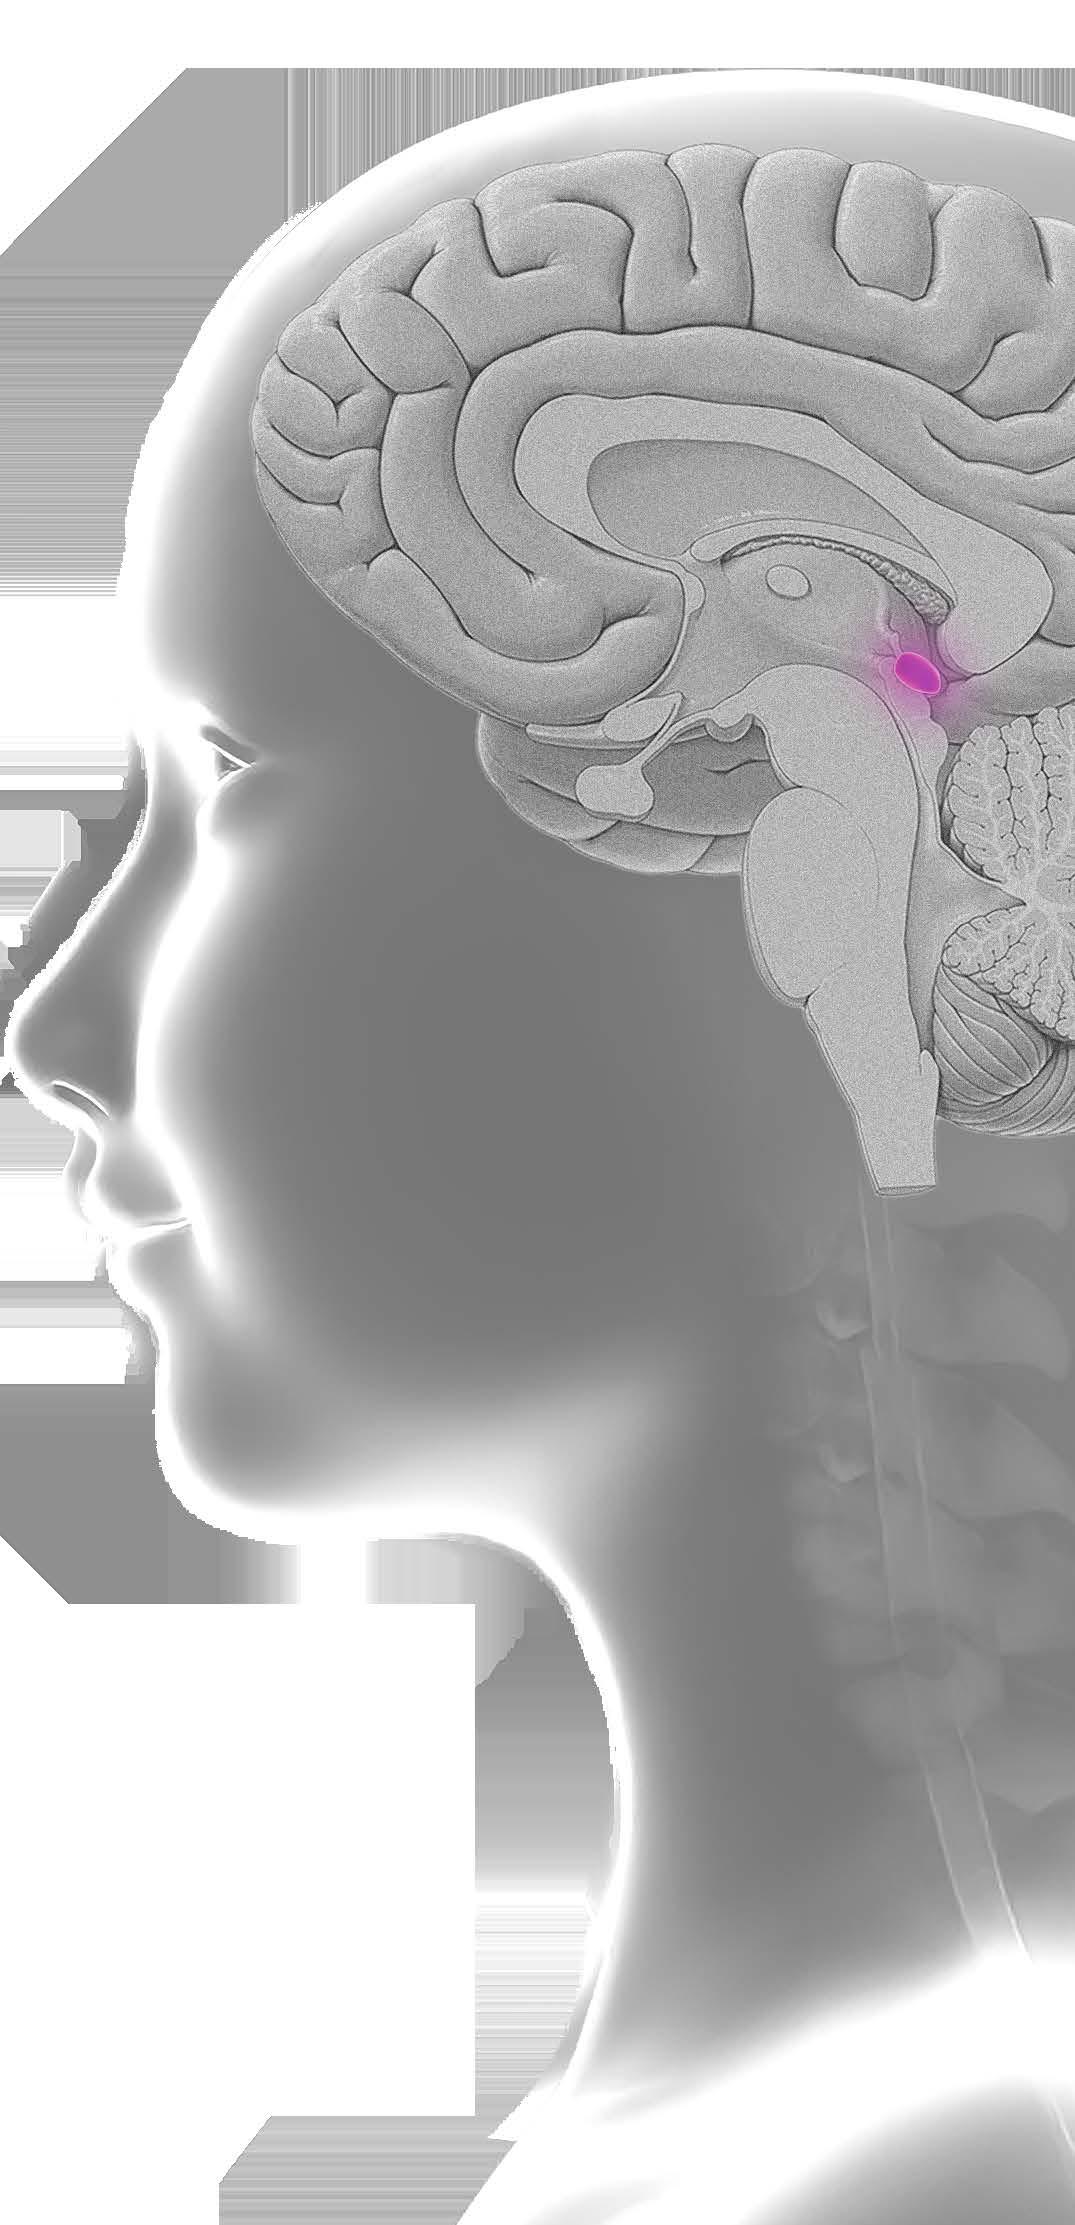

Los tumores primarios del sistema nervioso central (SNC) son la segunda causa más común de cáncer en edad pediátrica, excedido en incidencia por las leucemias y constituyen aproximadamente un cuarto de todas las neoplasias en niños.

Los GBG representan los tumores cerebrales más comunes en la edad pediátrica y constituye más del 20% de los tumores primarios cerebrales. La mayoría ocurren en el cerebelo, vías visuales y el diencéfalo. La incidencia de GBG en Estados Unidos se aproxima a 2 por 100,000 personas de 0 a 19 años de edad. Pueden estar asociados con síndrome de predisposición familiar de cáncer subyacente o síndromes neurocutáneos. Por ejemplo, niños con neurofibromatosis tipo 1 (NF1) tiene mayor riesgo de desarrollar GBG que involucren las vías visuales, encontrados en el 15 a 20 % de niños con NF1 y en niños con el complejo de esclerosis tuberosa (CET) tienen una mayor incidencia de astrocitoma de células gigantes subependimarias (SEGA por sus siglas en ingles), un subtipo de GBG.

Los GBG típicamente son tumores de crecimiento lento y la presentación clínica depende de la localización del tumor y la edad del paciente. Los síntomas resultan por la invasión al parénquima cerebral que lo rodea, compresión local del tejido cerebral o aumento de la presión intracraneal (PIC) generalizada. Los niños pueden presentar síntomas focales o difusos o una combinación de ambos. El aumento del a PIC puede producir dolores de cabeza, vómitos, irritabilidad y problemas de conducta. Los tumores en áreas elocuentes del cerebro pueden producir signos y síntomas focales que reflejan la función anatómica involucrada.

La cirugía es el pilar del tratamiento para la mayoría de GBG pediátrico. La cirugía provee el tejido para la interpretación histopatológica y la caracterización molecular. Cuando es posible la resección completa puede ser curativa. En niños, cuando se realiza la resección quirúrgica de la lesión, la sobrevida de progresión libre a 5 años es cerca del 90% mientras que más de la mitad de los niños con resección subtotal tienen recurrencia de la enfermedad durante ese intervalo.

La mayoría de los GBG, especialmente los de vías ópticas, tallo cerebral y otras estructuras de la línea media, pueden no ser candidatos para cirugía o resección completa y la terapia adyuvante logra el control del tumor y prolonga la sobrevivencia. El uso de quimioterapia antes de la radioterapia, al inicio del diagnóstico y en la recurrencia ha demostrado la eficacia de la quimioterapia que puede retrasar o